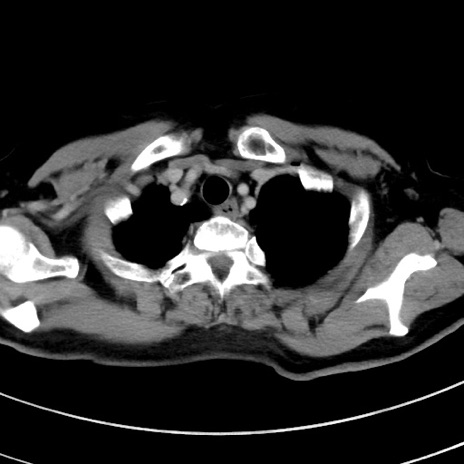

症例9(横断像)

【症例】 60歳代女性

【主訴】むかつき、みぞおちの痛み

【現病歴】3日前よりむかつきがあり、食事がとれない。

【既往歴】糖尿病

【身体所見】発熱なし、心窩部圧痛軽度あるも、腹膜刺激症状なし。

【データ】WBC 7400、CRP 1.92